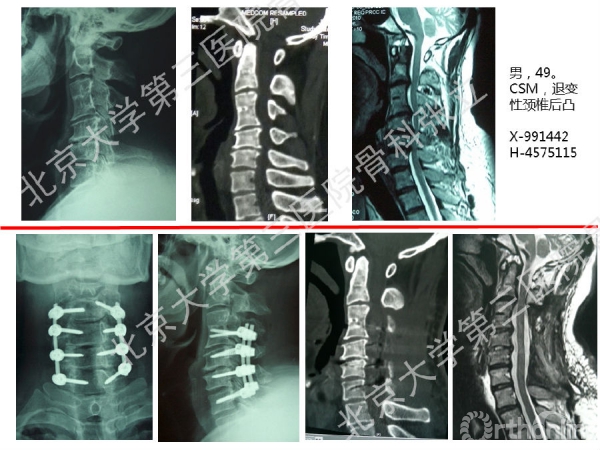

徒手置钉的下颈椎椎弓根钉技术对于很多骨科同道来说,无疑是难度超高、不敢触及的一项技术。已熟练掌握这一技术的北京大学第三医院骨科张立主任医师认为,下颈椎椎弓根钉徒手置钉技术固定可靠,能满足绝大多数后路固定所需,可应用于脊柱外伤、脊柱畸形、脊柱肿瘤,以及CSM伴退变性颈椎后凸畸形。它的优势是:螺钉尾部靠外,不影响椎板成形术;先置钉固定,后开门,更安全;和椎板成形术完美结合,减压、复位、固定一次完成;极少出现脊髓、神经根及椎动脉损伤。